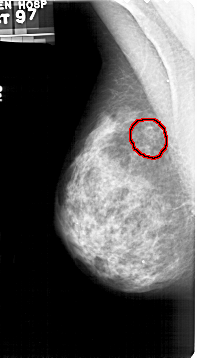

A_1427_1.LEFT_CC

LEFT_CC LINES 4861 PIXELS_PER_LINE 2791 BITS_PER_PIXEL 12 RESOLUTION 43.5 OVERLAY

FILE: A_1427_1.LEFT_CC.OVERLAY

TOTAL_ABNORMALITIES 1

ABNORMALITY 1

LESION_TYPE CALCIFICATION TYPE AMORPHOUS DISTRIBUTION CLUSTERED

ASSESSMENT 4

SUBTLETY 3

PATHOLOGY BENIGN

TOTAL_OUTLINES 1